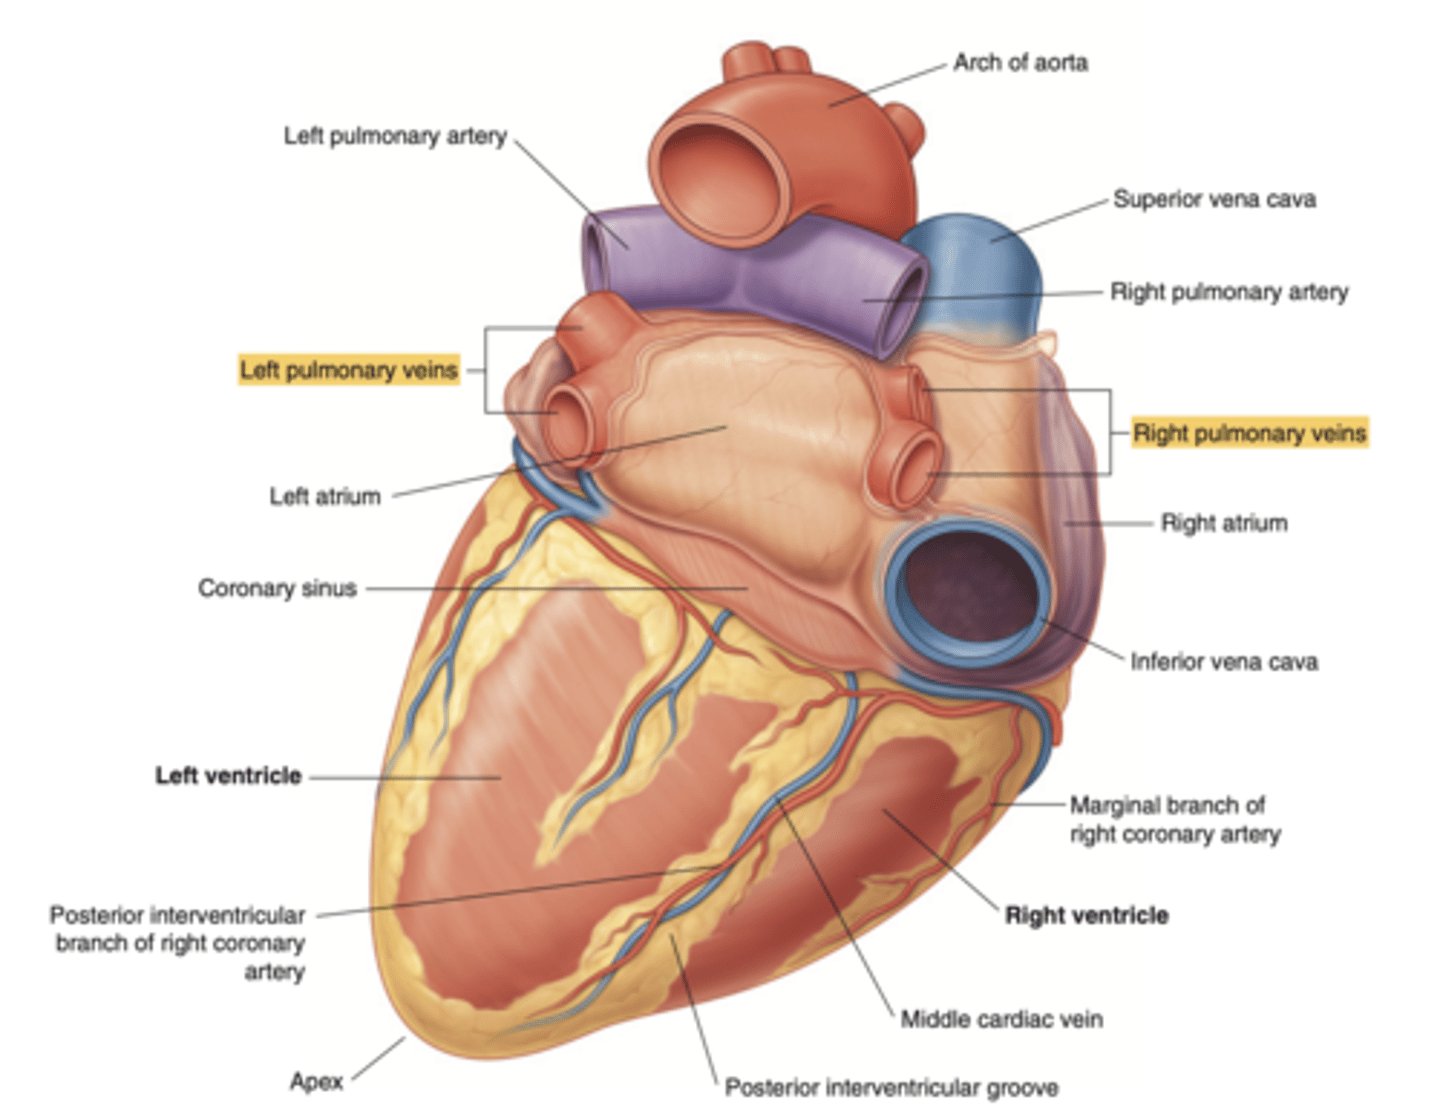

Which veins enter the left atrium?

left pulmonary veins

right pulmonary veins

ALLOWS OXIGENATED BLOOD FROM THE LUNGS TO ENTER THE HEART

What are the vessels incorporated to the atria?

cava veins (sinus venosus embryo origin, for the right one)

pulmonary veins (4, for the left one)